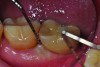

Fig 3. Clinical view of a maxillary left second premolar in an 73-year-old patient with a history of smoking. The tissue around the implant is quite inflamed and probes up to 8 mm with bleeding.

Figure 3